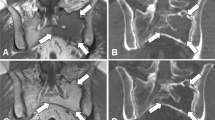

WB-MRI has superior soft tissue contrast to WB-LDCT and can demonstrate BM involvement, either focal or diffuse, prior to cortical bone destruction [27]. As a result, the IMWG [4] state that > 1 (i.e., 2 or more) focal lesion measuring ≥ 5 mm in size on MRI is a myeloma defining event (MDE). Guidelines for image acquisition, interpretation and reporting of WB-MRI in myeloma have been published [28] and recommend diffusion-weighted imaging (DWI), a functional imaging sequence, as part of a core clinical protocol. DWI reflects the free random motion of water, which becomes increasingly restricted with higher percentages of malignant PC infiltration, and manifests as high signal intensity on DWI sequences; this enables accurate differentiation from normal fatty BM and underpins the higher sensitivity of DWI for both focal and diffuse BM infiltration, compared to conventional MRI sequences [29]. Generic limitations of MRI include claustrophobia, which may be exacerbated by using large body coils for WB-MRI, non-MRI conditional implants and devices, and renal failure, if using gadolinium-based contrast agents. Limitations specific to WB-MRI, include greater cost and lower availability compared to WB-LDCT; PSMRI can be used in cases where WB-MRI is unavailable albeit with the potential to miss disease (10%) lying outside of this FOV [30]. WB-MRI is also time consuming, taking between 30–50 min to complete, and can be especially problematic for patients suffering from myeloma-related bone pain.

The sensitivity of [18F]FDG PET/CT for symptomatic MM is comparable/less than pelvic-spinal MRI (PSMRI) [41, 48, 49]. The first direct comparison of these two imaging modalities, albeit in a small series, revealed that [18F]FDG PET/CT sensitivity was lower than PSMRI for diffuse BM involvement but it did allow additional FLs to be detected, in particular, those outside of the the MRI FOV [48]. Results from the prospective IMAJEM study published in 2017 compared conventional PSMRI and [18F]FDG PET/CT at initial diagnosis and after therapy; 94.7% of PSMRI-scanned patients and 91% of [18F]FDG PET/CT patients were positive, demonstrating equivalent sensitivity [41]. More recently, a retrospective comparative study of 46 NDMM patients reported that WB-MRI detected bone disease with a higher per patient sensitivity compared to [18F]FDG PET/CT (91.3% vs. 69.6%). Interestingly, the clinical treatment decisions for these patients were very similar and either modality was appropriate for initial staging.[50]. Finally, we and others [51, 52] recently showed that WB-MRI with DWI improves the sensitivity for FL detection, which is higher than [18F]FDG PET/CT, especially in SMM patients at initial diagnosis.